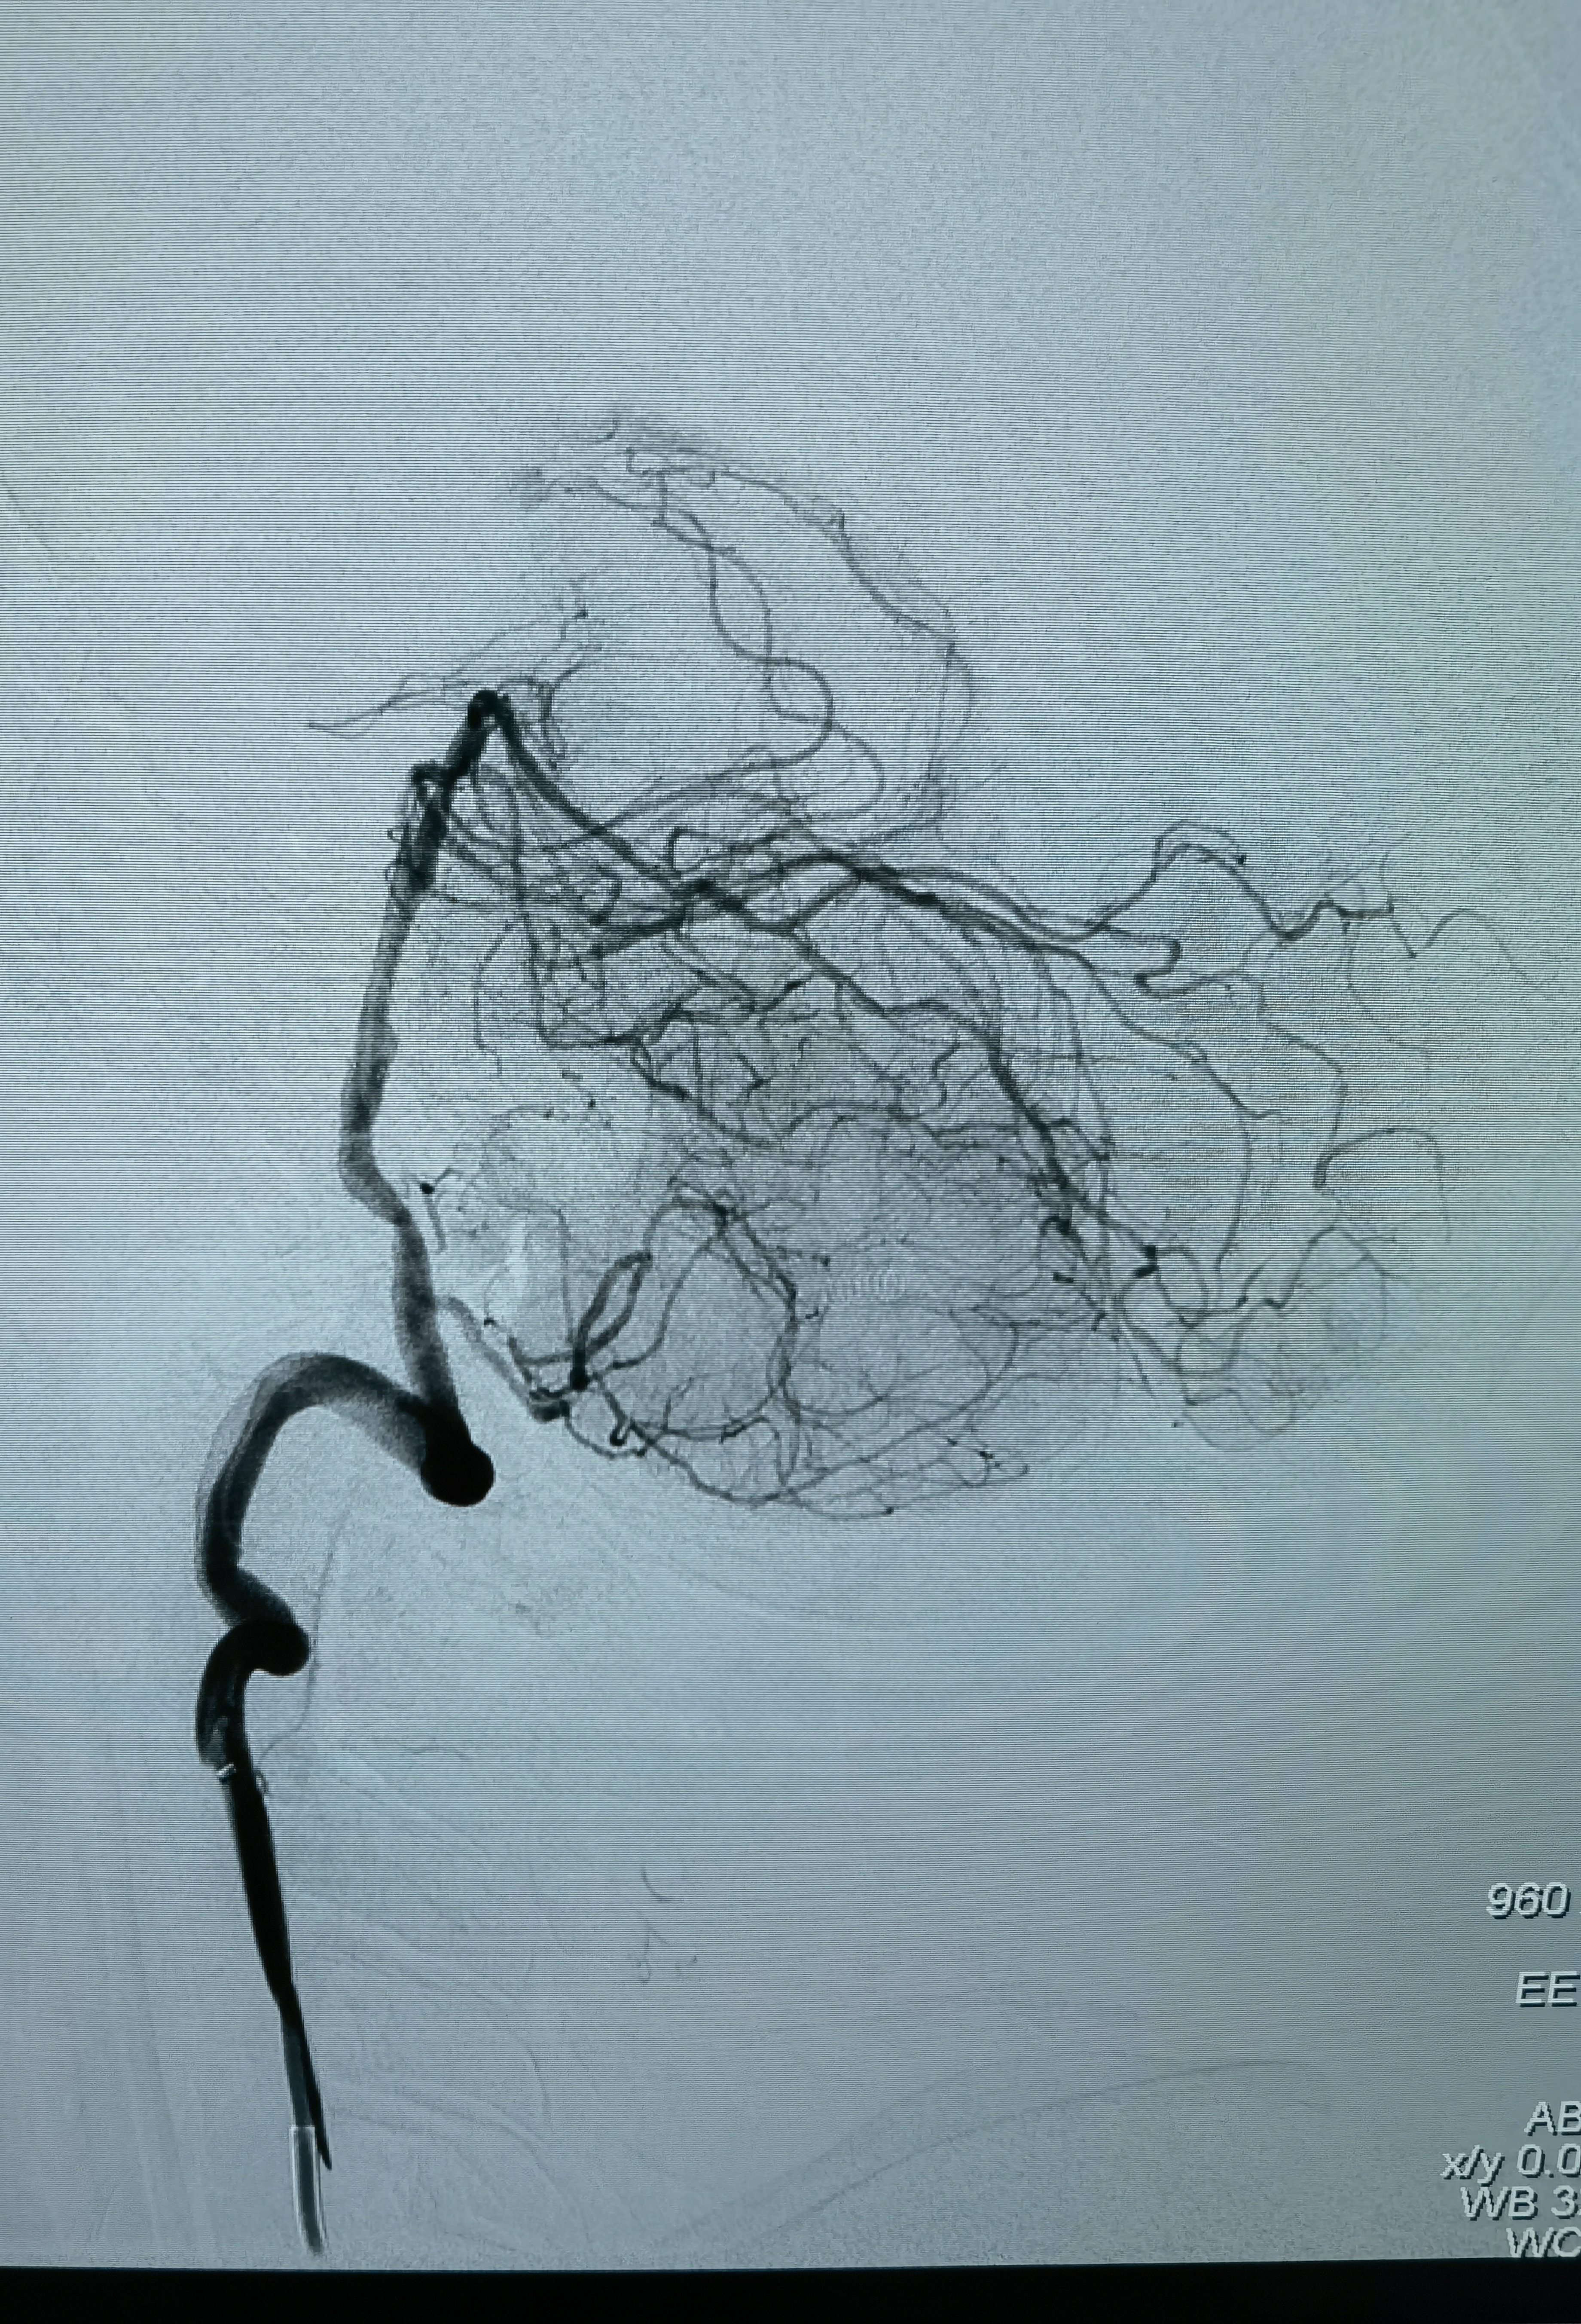

旋转造影

工作位造影

狭窄85%